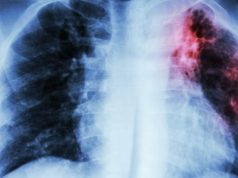

MITI&SALUTE/ Immigrati e malattie: il falso allarme tubercolosi

LECCE (di Italo Aromolo) - Il dibattito sull'immigrazione sarebbe degno della più alta e perfetta forma di società politica, tanto è il fervore che...